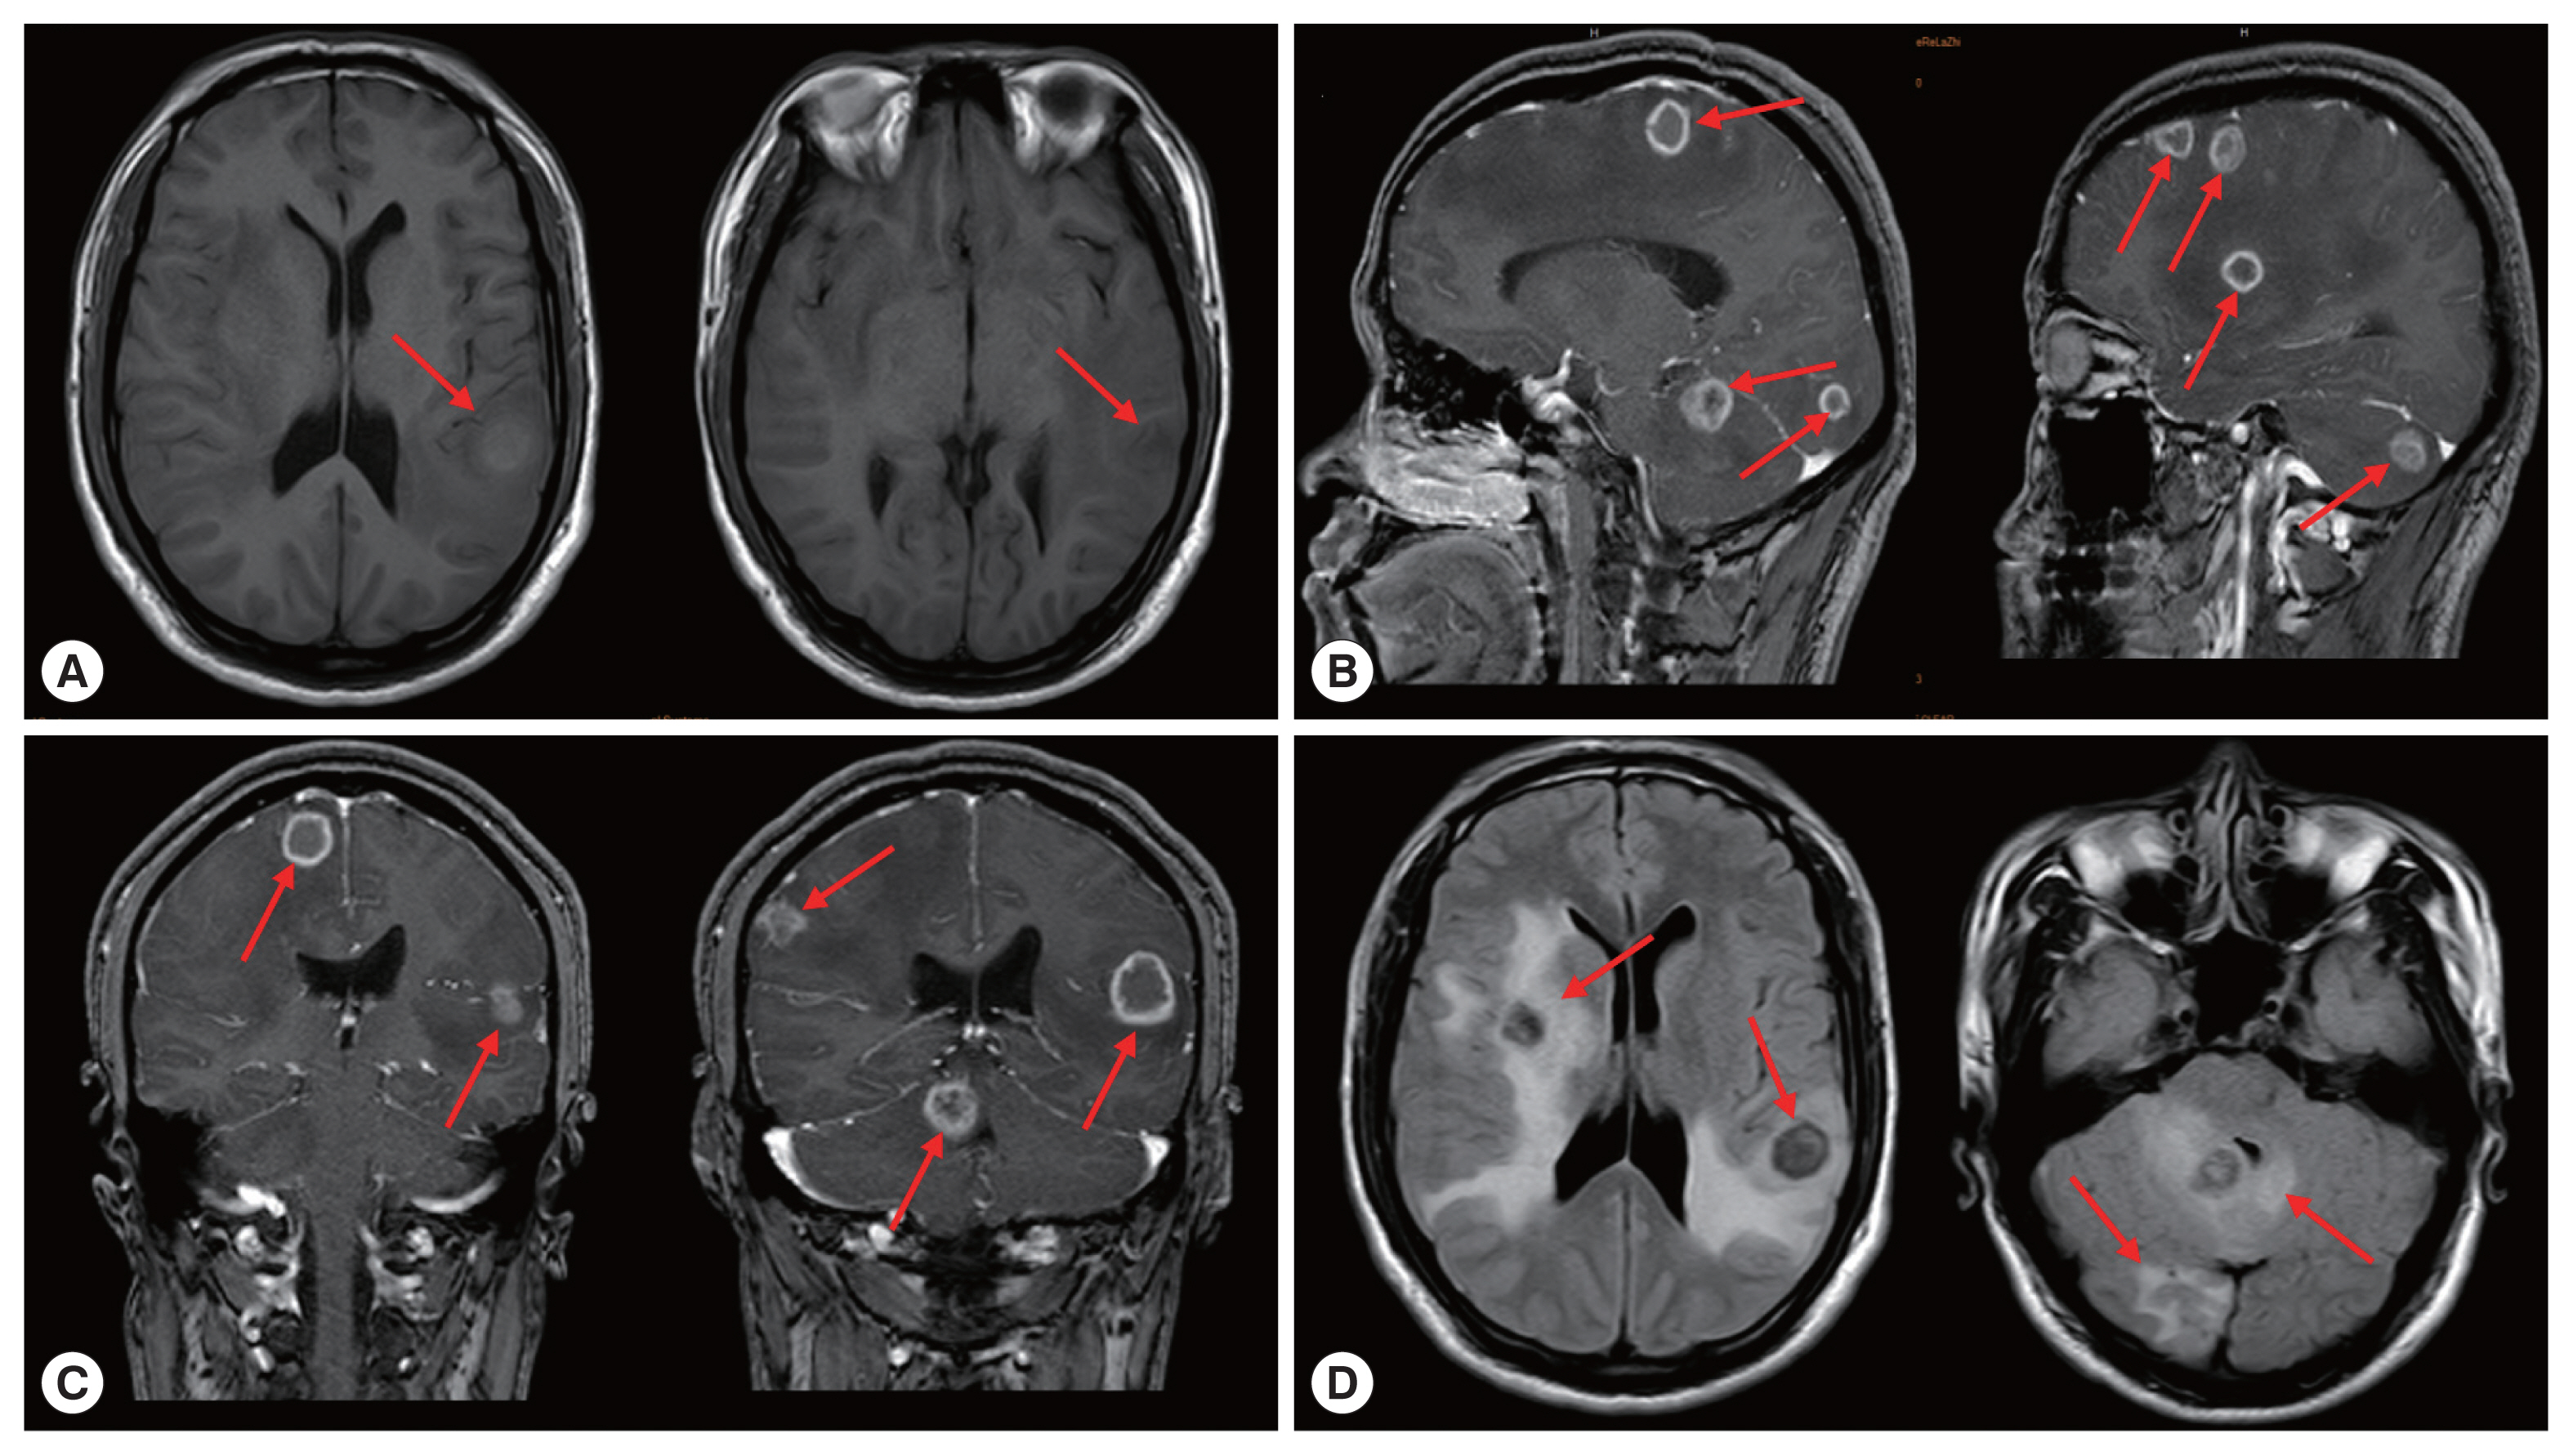

On March 30, 2020, the patient came to the neurosurgery department of our hospital again due to unprovoked dizziness and headache for 2 weeks. The patient suspected that he had an upper respiratory tract infection and took oral medication to treat it by himself (the specific medication was unknown). In the past 1 week, accompanied by nausea and vomiting, the patient had frequent headaches and blurred vision in his right eye. Physical examination of right limb muscle strength gave grade IV, and unclear vision in right eye. Brain CT images showed multiple round lesions in the brain parenchyma (Supplementary Fig. S1). According to MRI examination, there were multiple short T2 and other T1 signal lesions in the brain parenchyma with ring enhancement in the brain parenchyma, and obvious edema around the lesions (Fig. 3). The patient’s vital signs and laboratory tests were in the normal range. Combined with the patient’s medical history, the patient was clearly diagnosed as cerebral AE metastasized from the primary lesion. The multiple AE lesions in the brain were in the regions difficult to remove by operation. In addition, the patient had a grand mal seizure during hospitalization. When informing the current condition to his family members, they gave up further treatment and discharged the patient. At discharge, we recommended that the patient to take albendazole 400 mg twice a day for life

The clinical symptoms of brain AE depends on the degree of damage to central nervous system, including common symptoms of increased intracranial pressure, epilepsy, neurological disorders (such as blurred vision and paralysis), and cranial nerve palsy [21]. The CT and MRI of cerebral AE are mostly solid or multilocular cystic masses with clear boundaries, accompanied by calcification and peripheral edema [4]. Our patient also presented obvious nervous system involvement. CT and MRI of the patient showed multiple solid intracranial lesions with edema. The incubation period of AE infection is about 5–15 years, during which there are no obvious clinical symptoms. The patient’s brain lesions may have been metastasized due to liver lesion or rupture of a lung abscess. The patient currently depend on taking albendazole oral treatment for a long time. Albendazole can penetrate the blood-brain barrier more than mebendazole and is also the first choice of chemotherapy drugs for brain AE [22].